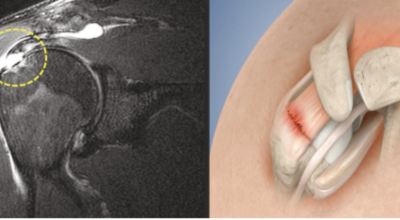

회전근개 증후군은 회전근개에 변형과 파열이 발생된 질환을 말합니다. 회전근개란 어깨와 팔을 연결하는 4개의 근육(극상근, 극하근, 소원근, 겹갑하근) 또는 힘줄로 이루어져 있는 것으로 보입니다. 어깨 근육통을 막연히 오십견으로 알고 방치하다가 치료 시기가 늦어지는 경우가 있습니다. 적절한 시기에 병원에 가는 것이 필요합니다.

회전근개가 파열되는 경우 어깨에 통증이 생기게 되어요. 회전근개는 어깨 회전 운동에 영향을 줌으로써 팔을 들어올리는 동작에 제약이 생기기도 합니다. 이러한 증상은 오십견 증상과 비슷하기도 한데요. 수동적 움직임도 제한되는 오십견과는 달리 다른 사람의 도움을 받게 되면 팔을 들어올릴 수 있다는 차이가 있답니다.